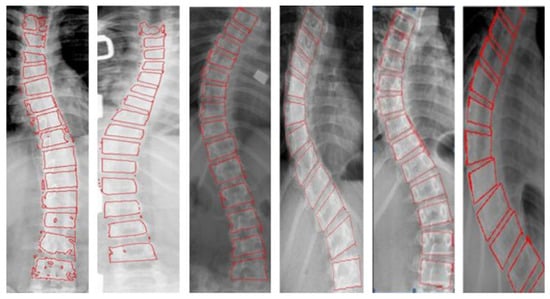

4.2.1. Segment the Vertebral Body to Measure the Cobb Angle

4.2.2. Locate the Landmark of the Spine to Measure the Cobb Angle